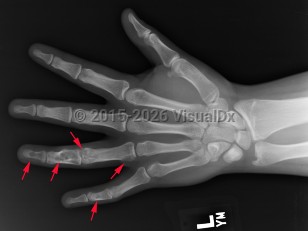

Classic history and presentation: The proximal phalanx is the typical location. These tumors are also common incidental findings in the distal femur, proximal humerus, and tibia. Mean length is usually less than 5 cm.

Prevalence: Enchondroma is a latent lesion that comprises 15%-25% of cartilage tumors. It is the most common hand tumor, accounting for 90% of cases. Enchondroma usually presents in the third and fourth decades of life and occurs equally between both sexes.

Pathophysiology: Enchondroma pathophysiology is believed to involve incomplete endochondral ossification in which physeal remnants become entrapped in the medullary cavity of the metaphysis and proliferate. In the hand, enchondromas are typically diagnosed after a pathologic fracture. Elsewhere, they are typically an asymptomatic incidental finding on x-ray or advanced imaging performed for other reasons. Pain is usually due to a nearby abnormality rather than the tumor itself.